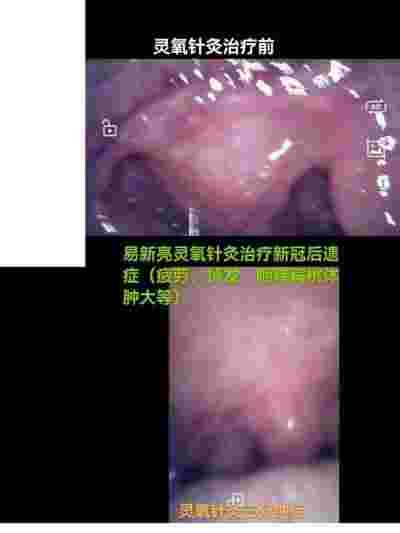

不仅如此,易新亮医师还运用其独特的针灸技艺,成功治疗了新冠病毒留下的各种后遗症,为众多患者带来了新的希望。对于三高、糖尿病等慢性疾病,他更是提出了断药治疗的创新思路,让患者能够摆脱长期服药的困扰。咽炎、支气管炎、肝炎、前列腺炎,以及风湿、类风湿、干燥综合征等顽疾,在他的疗法下也得以断根,重获健康。